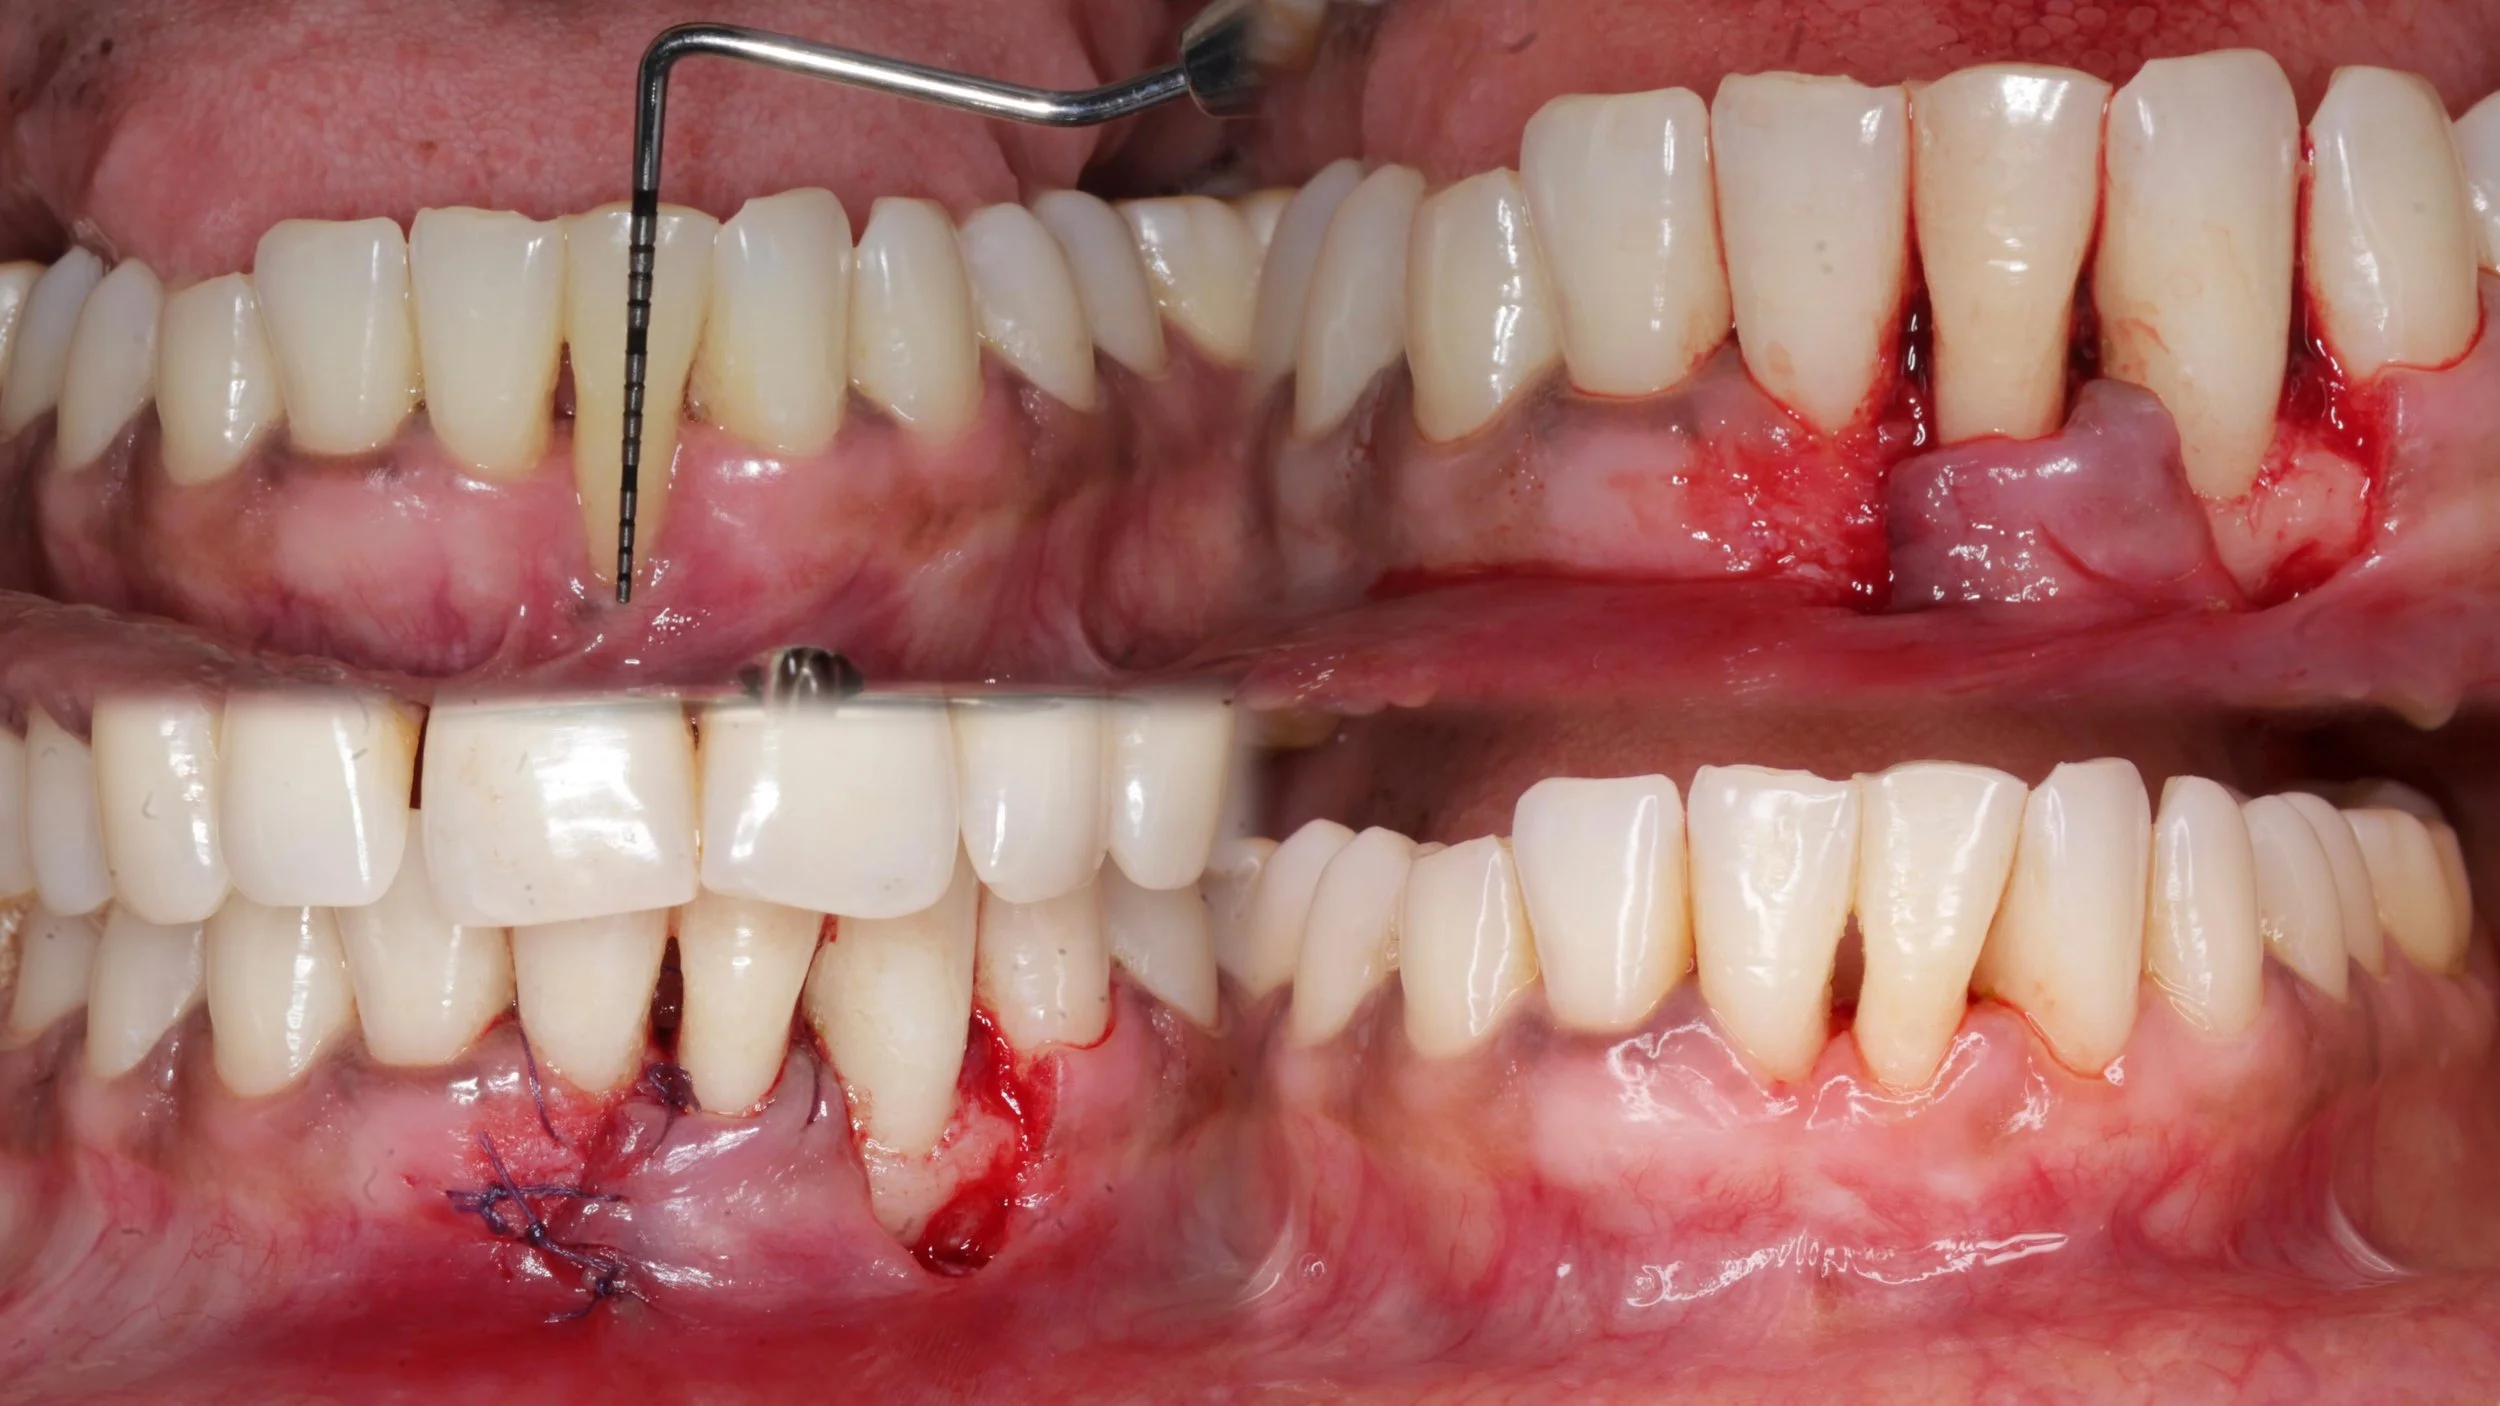

ROOT COVERAGE WITH CORONALLY ADVANCED FLAP

Surgery performed by Dr Poulami